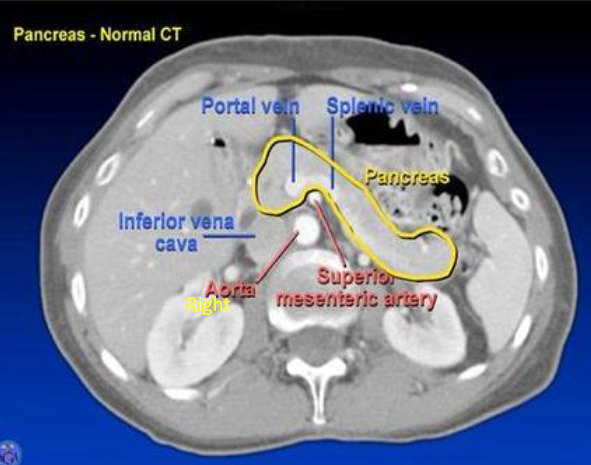

what does a pancreatic CT shown?

tail → @ splenic hilum

head → @ IVC

body → @ aorta + SMA